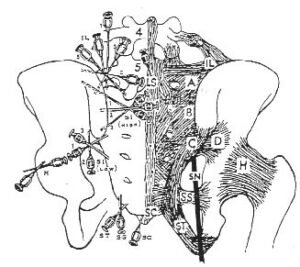

Needle Location used for injection of the sacroiiac ligaments. Trigger point of ligaments: (IL) Iliolumbar; (LS) Lumbosacral-supra and interspinus; (A,B,C,D,) Posterior sacroiliac; (SS) Sacroapinus; (ST) Sacrotuberus;(SC) Sacrococcygeal;(H) Hip-Articular; (SN) Sciatic nerve (from G.S. Hackett, Ligament and Tendon Relaxation. Charles C. Thomas Co., 1958)

Sacroiliac joint prolotherapy is sometimes used to treat sacroiliac joint pain. Protocols vary for thisProlotherapy, also known as “proliferative therapy” or “regenerative injection therapy,” is another non-surgical option for SI joint pain. This treatment involves injecting a solution (usually dextrose or other irritants) into the ligaments and tendons around the sacroiliac joint.